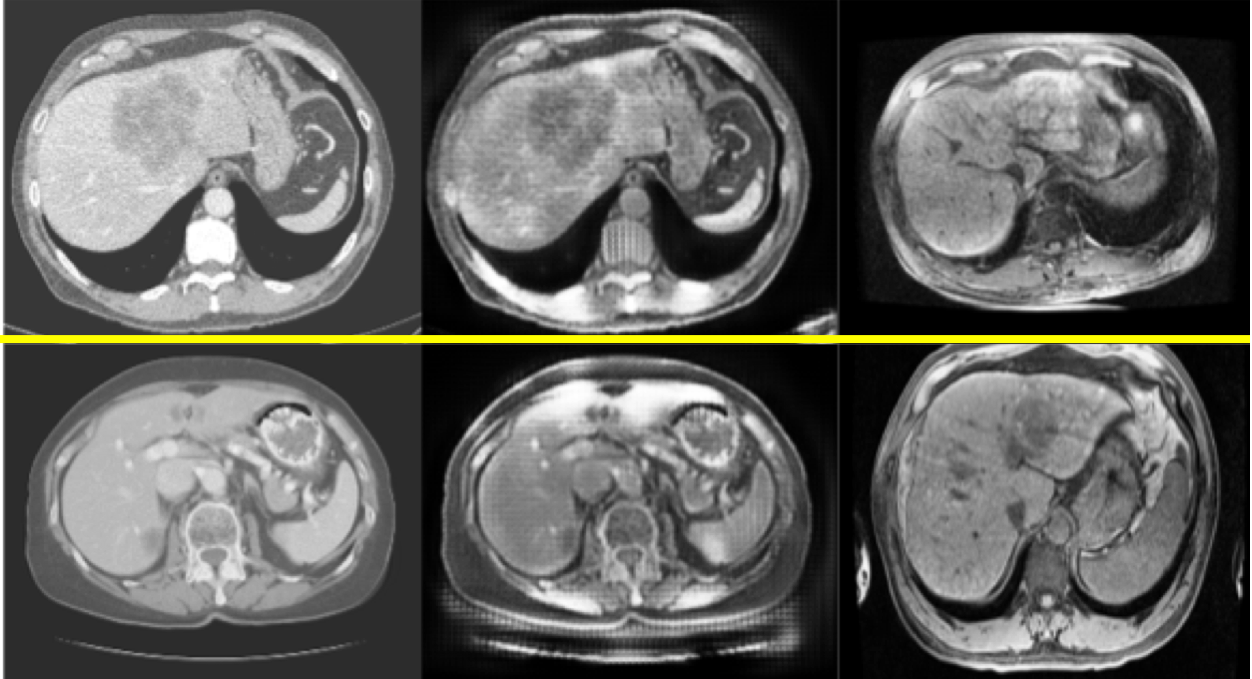

Given the significant domain shift, cross-modality domain adaptation is quite difficult (see Fig. 1). One promising approach utilizes CycleGAN, a pixel-wise style transfer model, for cross-modality domain adaptation in a segmentation task [3]. Compared to feature-based domain adaptation, it does not necessarily maintain the semantic feature-level information. More importantly, the cycle-consistency loss implies a one-to-one mapping between source domain and target domain and leads to lack of translated output diversity, generating very similar images. It thus fails to represent the complex real-world data distribution in the target domain and likely degrades the performance of segmentation or other follow-up analysis [5].

Refer to caption

Figure 1: Images and histograms of liver (yellow) and whole image (blue). From left to right: CT, multiphasic MRI sequence at three time points (pre-contrast, 20 seconds post-contrast i.e. arterial phase, 70 seconds post-contrast i.e. portal venous phase)

We tested our methods on unpaired CT slices of 130 patients from LiTS challenge 2017 [1] and multi-phasic MRI slices of 20 local patients with HCC (see Fig. 1). CT and MR were divided into 5 folds for subject-wise cross-validation. A supervised UNet [10] trained and tested on pre-contrast MR serves as upper bound of domain adaptation, while a supervised UNet trained on CT and tested on pre-contrast MRI, without domain adaptation, provides the lower bound, which shows the relatively large domain shifts between CT and MRI (see Table 2).